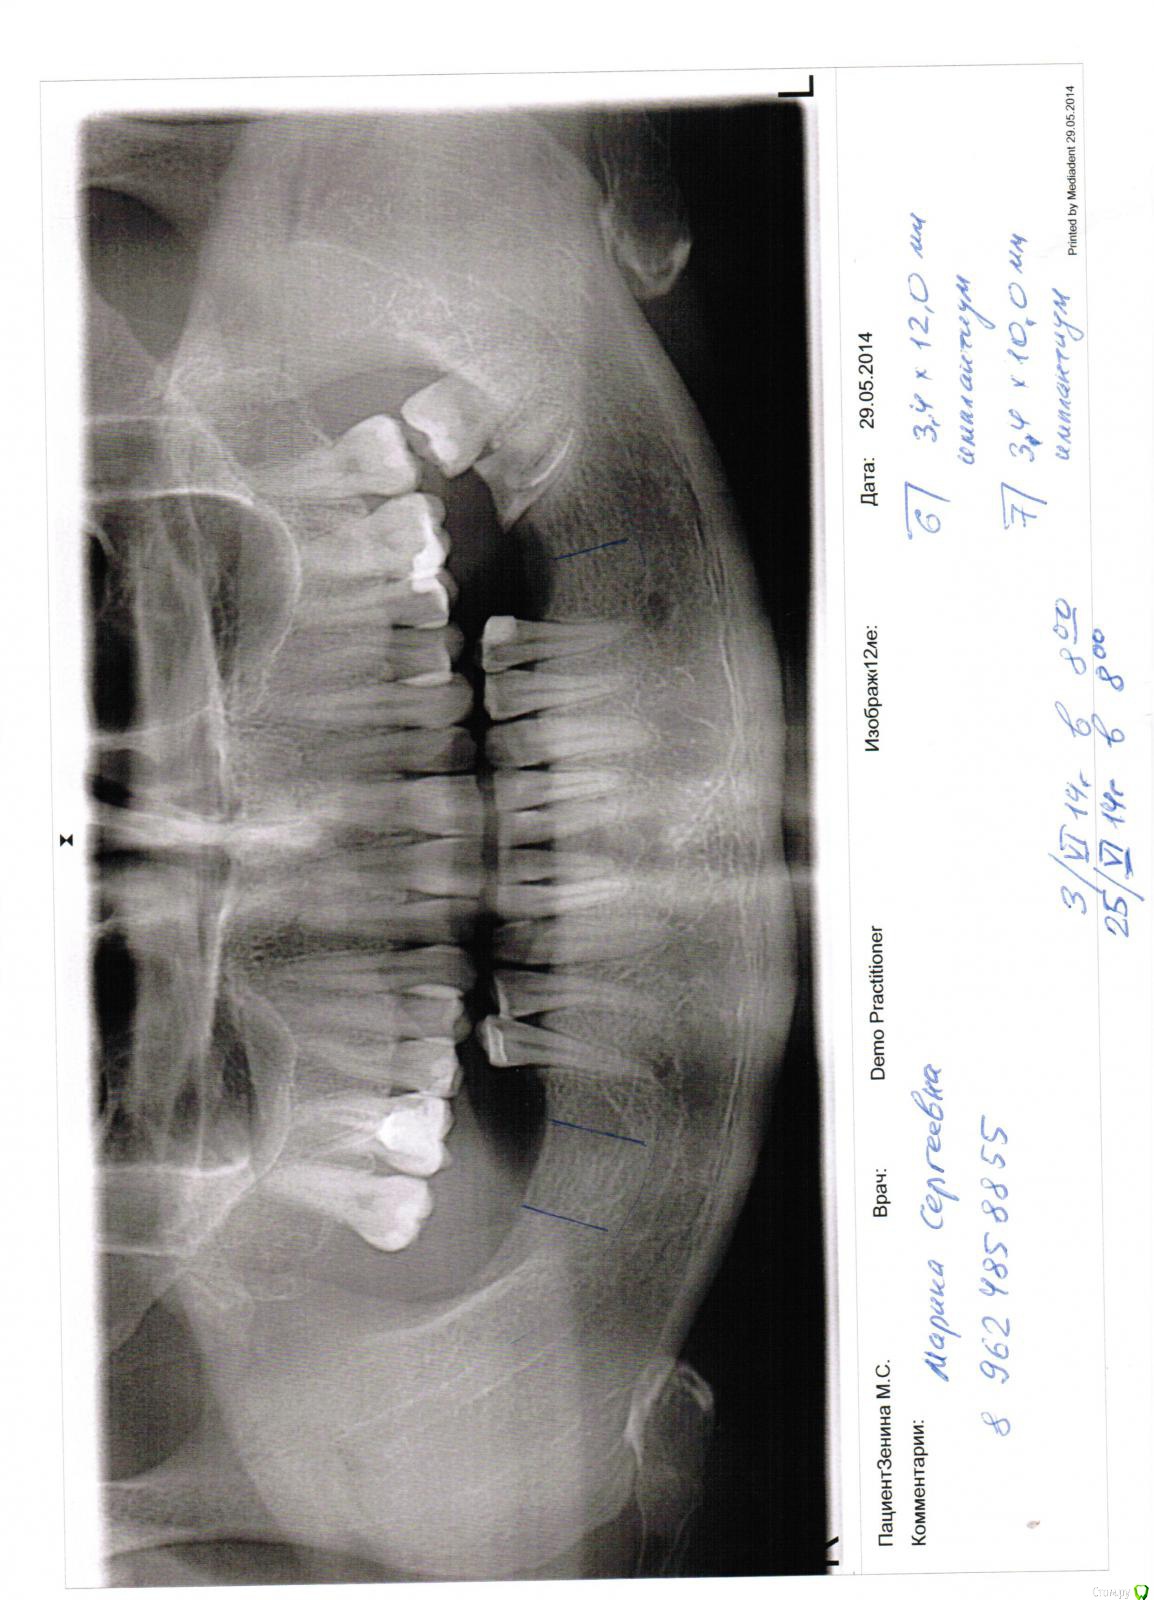

марин зенина Опубликовано 31 декабря, 2014 Автор Поделиться Опубликовано 31 декабря, 2014 (изменено) вот снимок. как то иголкой тыкали в десну еще и все. Изменено 31 декабря, 2014 пользователем марин зенина Ссылка на комментарий

марин зенина Опубликовано 31 декабря, 2014 Автор Поделиться Опубликовано 31 декабря, 2014 а вообще то такие тонкие импланты ставят или нет на жевательные зубы? Ссылка на комментарий

марин зенина Опубликовано 31 декабря, 2014 Поделиться Опубликовано 31 декабря, 2014 Всем доброго времени суток! У меня вопрос к специалистам в области имплантации. Консультировалась в 5 клиниках и только в одной сказали, что нельзя такой узкий имплант ставить на жевательные зубы. Вобщем, ситуация такая. У меня нет 6.7.8 на нижней челюсти с одной стороны и с другой стороны нет 6. на одной стороне сказали, что точно наращивание кости, а с другой сказали можно на 6 - 3.4*12мм и на 7 - 3.4*10мм. 4 имплантолога готовы были поставить мне эти импланты и лишь одна сказала, что такие узкие нельзя ставить, т.к. они года через 2-3 начнут шататься. Скажите, пжста, это реально так? Ссылка на комментарий